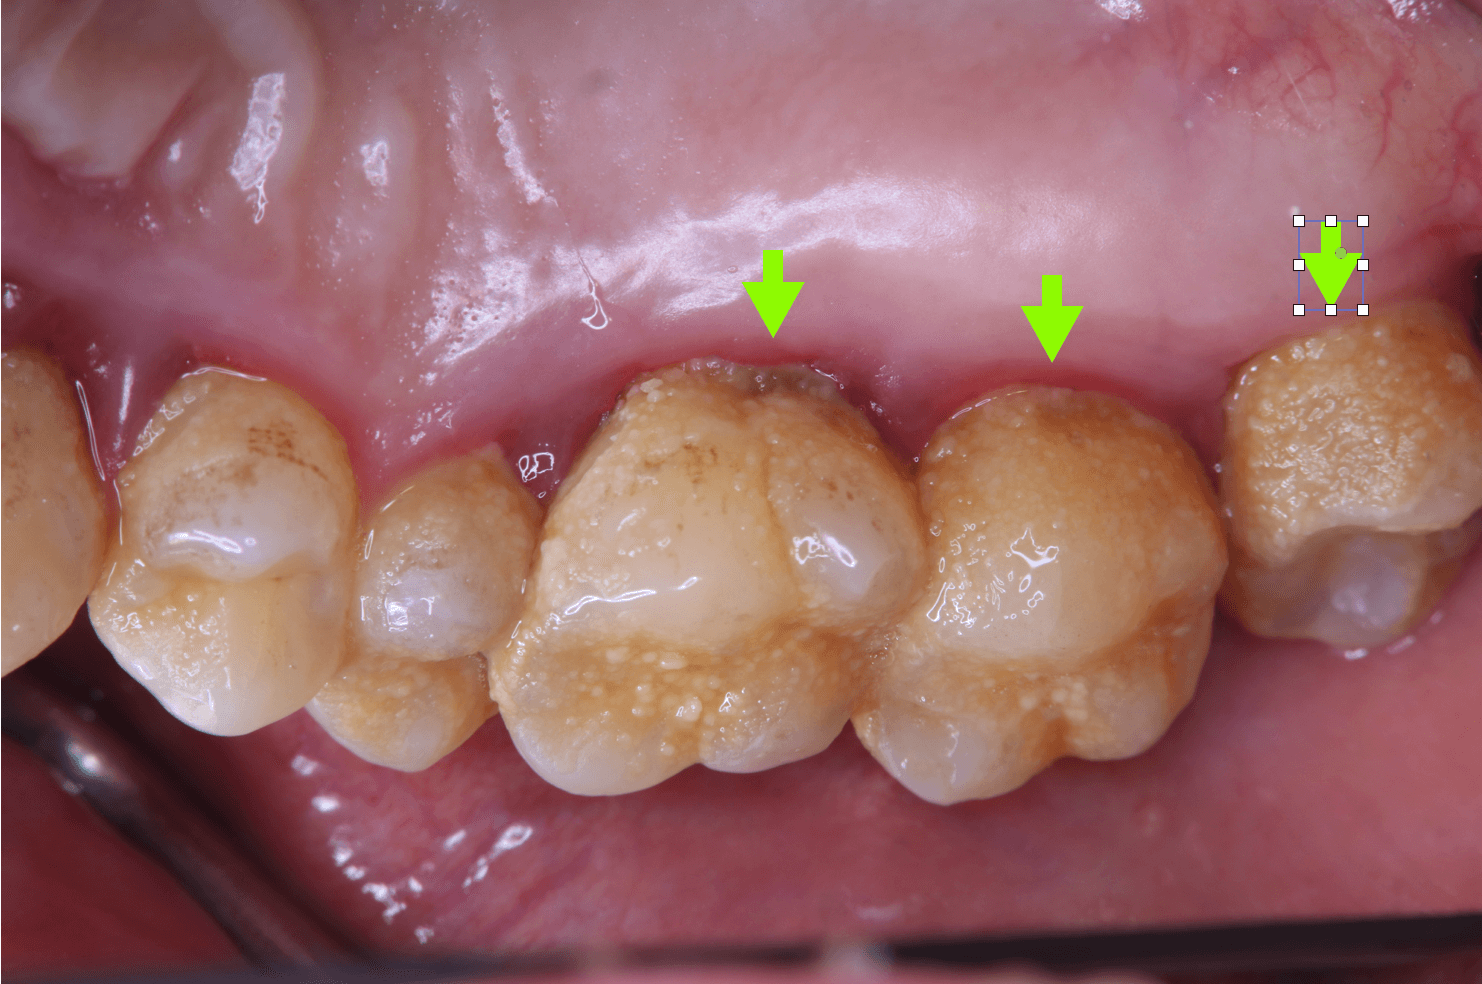

歯垢・歯石: 歯垢(プラーク)や歯石がたまると細菌の温床となり、口臭の原因となります。食べ物の残りかすや細菌が歯の表面に付着して歯垢が形成されます。適切に除去されないと、歯垢は硬化して歯石となり、さらに細菌が繁殖しやすい環境が作られます。これが歯周病を引き起こし、悪臭を発生させます。

歯周病:歯肉炎や歯周炎などの歯周病は、周病は歯茎の炎症を引き起こし、歯茎が下がることで歯周ポケットができ、そこに細菌がたまりやすくなり、出血や膿の原因となります。この膿が強い悪臭を放ちます。